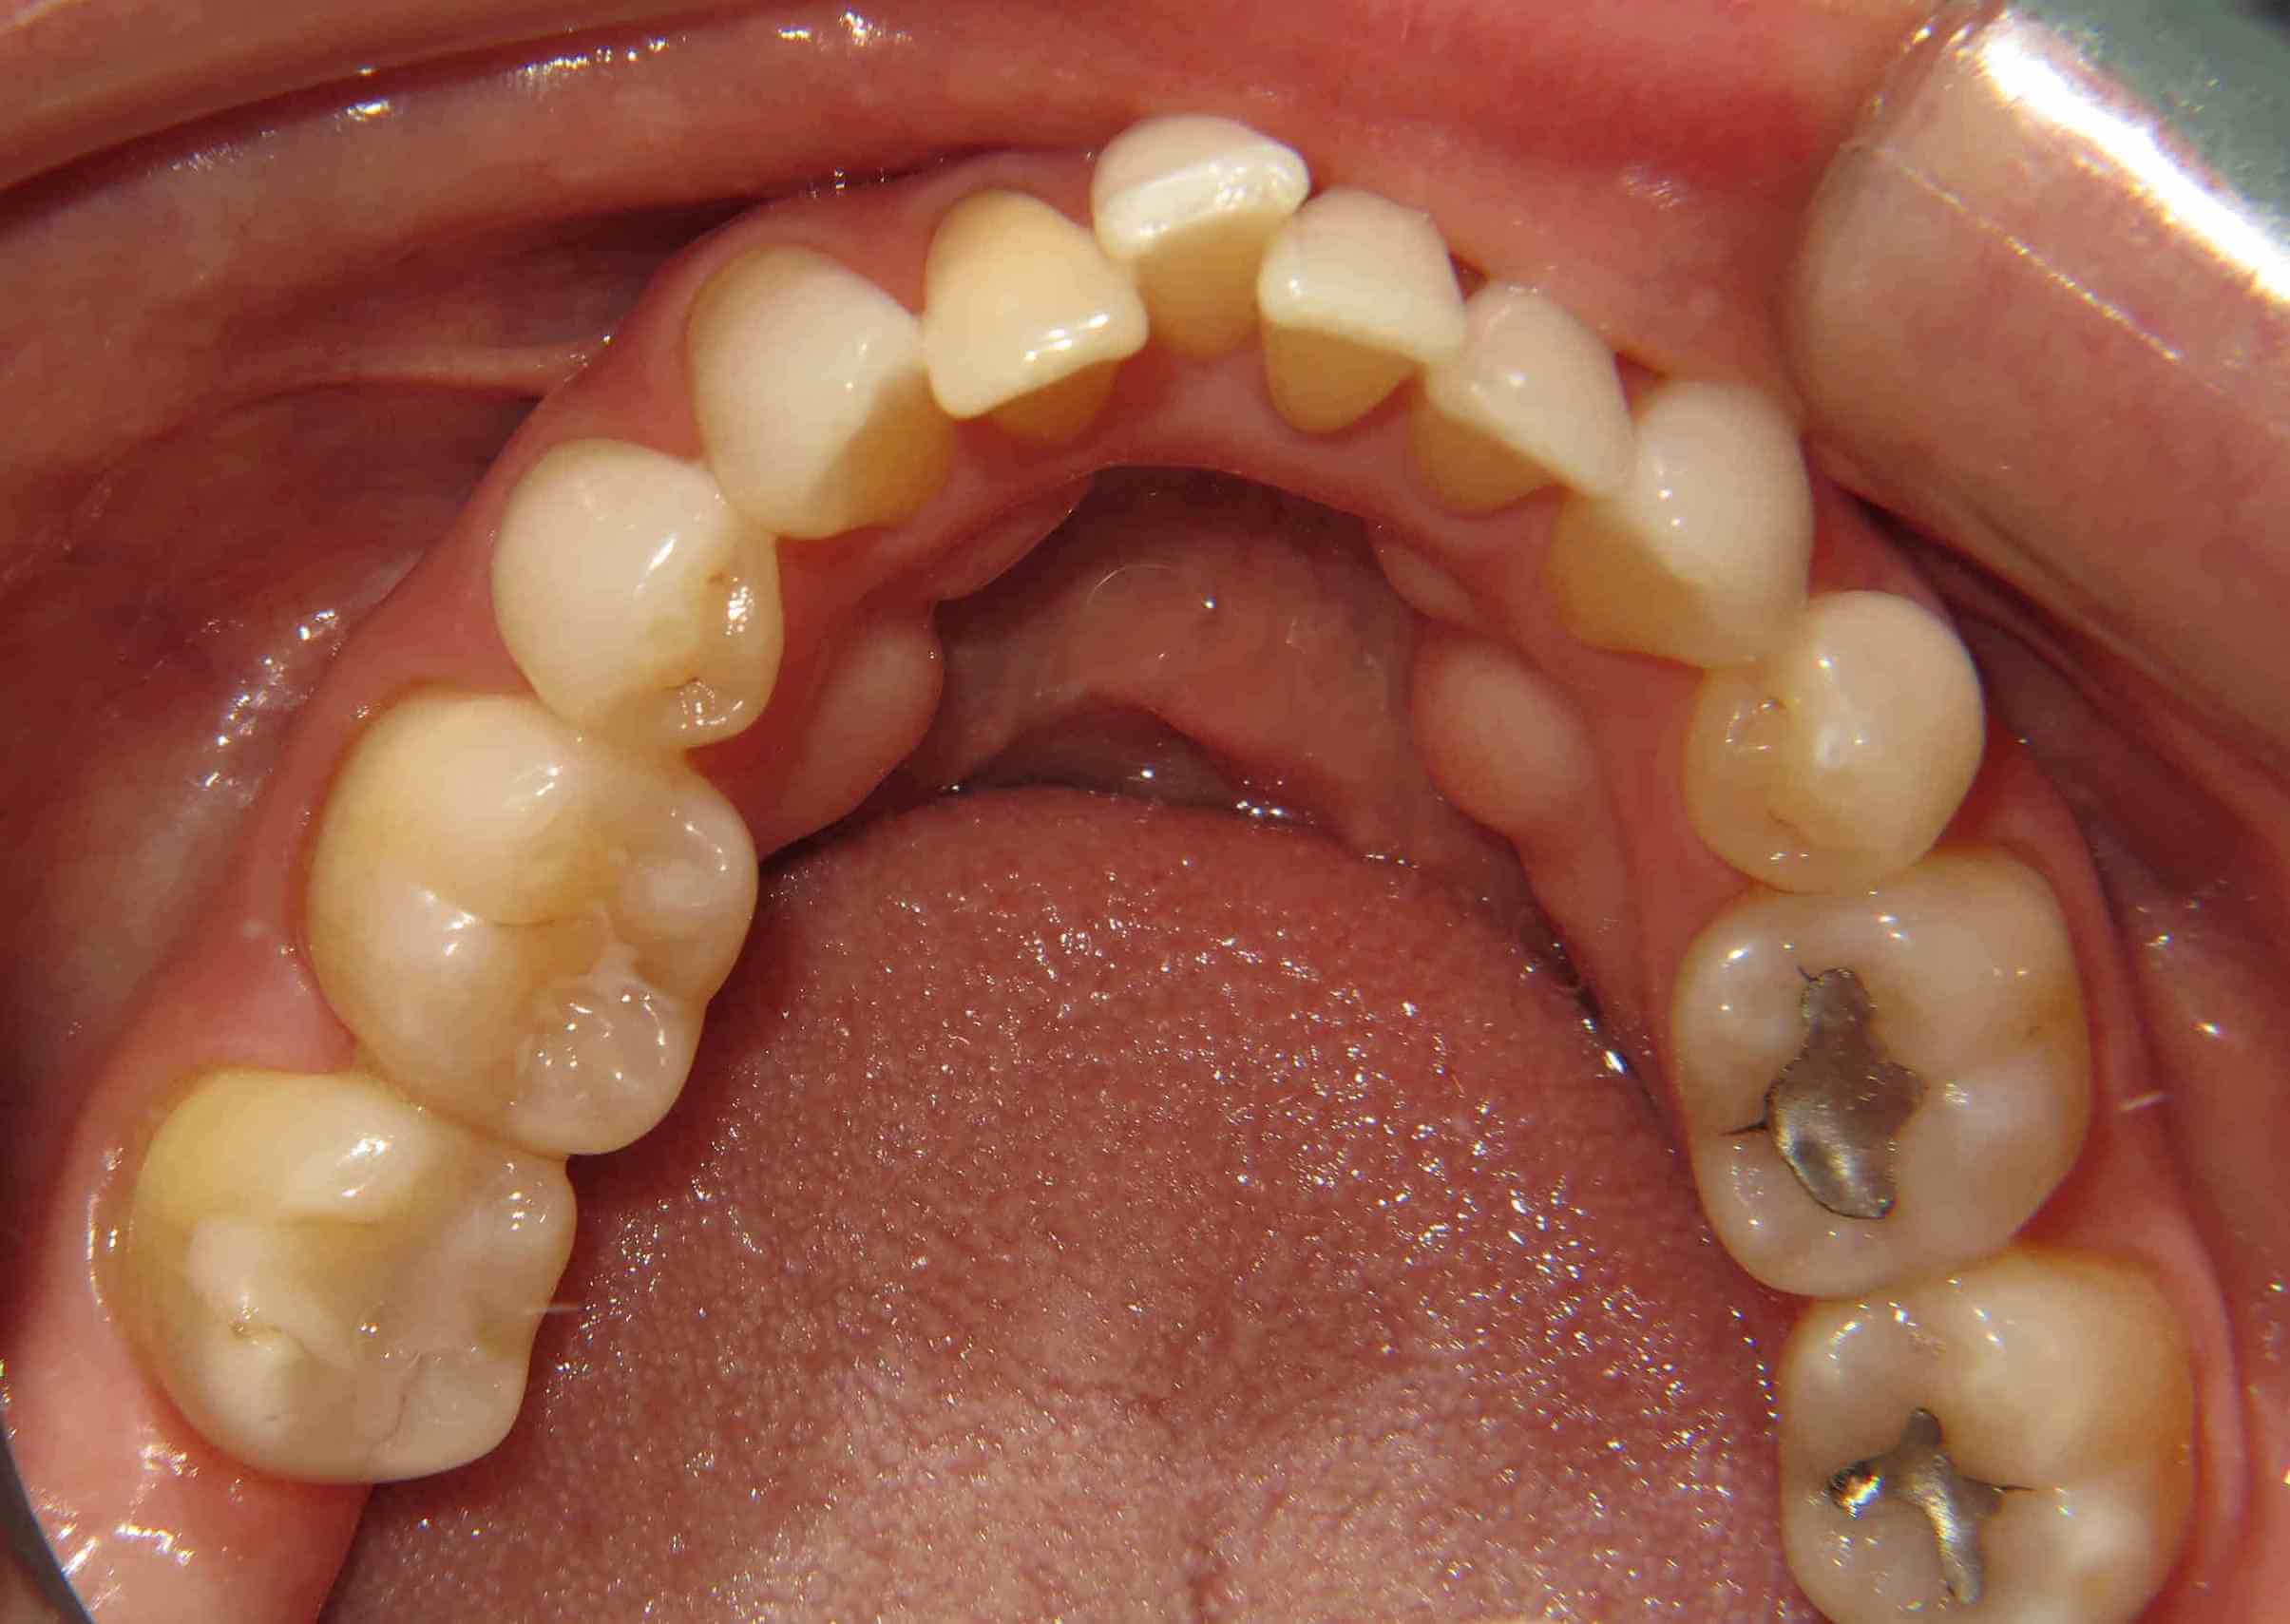

Female from Plano, TX gets Clear Correct Aligner Therapy now has great smile!